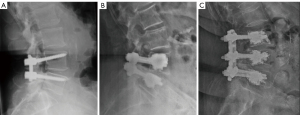

The 154 patients were divided into two groups according to their age at the time of the operation. Group 1 included 87 patients who were 65 years of age or younger (mean, 49.1 years; range, 24–65 years) and Group 2 included 67 patients who were 75 years of age or older (mean, 77.8 years; range, 75–86 years). All patients in Group 2 (age ≥75 years) underwent decompression and one- or two-level posterolateral (PL) instrumented fusion with cemented PMMA pedicle screw augmentation (Omega-21-LP pedicle screw, 6.35 - Zimmer Biomet. Warsaw, Indiana, US; Biomet bone cement V, Biomet Orthopaedics, Dietikon, Switzerland). Patients in Group 1 (age ≤65 years) underwent decompression and instrumented posterolateral instrumented fusion (PLIF) as indicated by the responsible surgeon (Polaris™ LP pedicle screw - Zimmer Biomet. Warsaw, Indiana, US) Fresh-frozen allograft bone was used in all cases for posterolateral fusion (Figure 1).

The main risk of using PMMA is the possibility of cement leakage. The reported incidence of cement leakage in augmentation techniques varies from 5% to 80% (38-40). Even though the incidence of cement leakage is very high, it is not necessarily clinically relevant. Widespread use of vertebroplasty has enabled surgeons to gain experience with the technique and has provided consistent data on the low risk of cement leakage when cement injection is performed in a controlled fashion (41-43). Cannulated pedicular screws make it possible to perform screw augmentation once the screws are inserted as well as to precisely control the consistency, rhythm, and volume of the cement injected into each screw. Cement is injected during the “toothpaste-like” phase to minimize the risks of extravasation. To decrease the cement leakage rate, some recommend the use of high-viscosity cement (44,45). We mostly use 55- and 50-mm screws in the lumbar spine, attempting to insert the tip of the screw as far as possible in all cases (46). Distal fenestration allows the delivery of the entire volume of cement into the vertebral body around the distal third of the screw, far ventral to the neurocentral canal. This distal concentration of cement for screw augmentation promotes a higher force to failure and diminishes the risk of cement extrusion into the spinal canal owing to an accidental pedicle breach (1,47-49). Intraoperative live fluoroscopic images demonstrate progressive symmetrical filling of the vertebral body. Based on the experience of the authors, 3 cc of cement per screw is injected in the lumbar spine and 2 cc in the thoracic spine, depending on the size of the vertebrae. None of the clinical complications observed in this study were related to cement leakage (Figure 2).